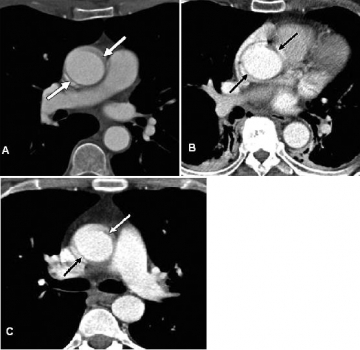

Hình 11: Ảnh giả do cử động của động mạch chủ. Hình axial qua ngực ở ngang mức động mạch phổi phải (a), gốc động mạch chủ (b) và động mạch phổi gốc (c) cho thấy ảnh giả do cử động của động mạch chủ (mũi tên) giống vành bóc tách ở động mạch chủ lên.